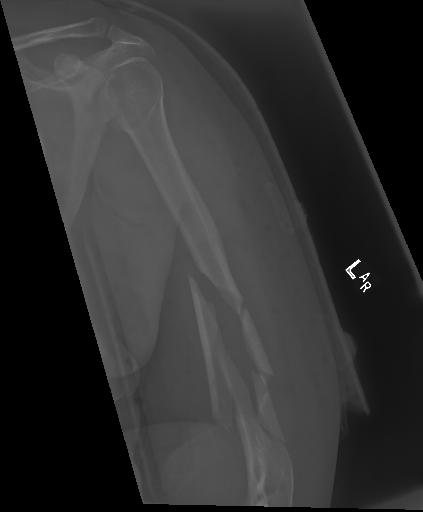

Bone 이미지 데이터 350장 중 Fracture 이미지 50장, Implant 이미지 50장, Bone 이미지 50장을 선별했다.

train과 val은 라벨링을 해야한다. 어제 라벨링을 했었지만, Fracture는 좀 넓게 잡고, Implant는 최대한 여러개로 쪼개는 느낌으로 라벨링을 다시했다.